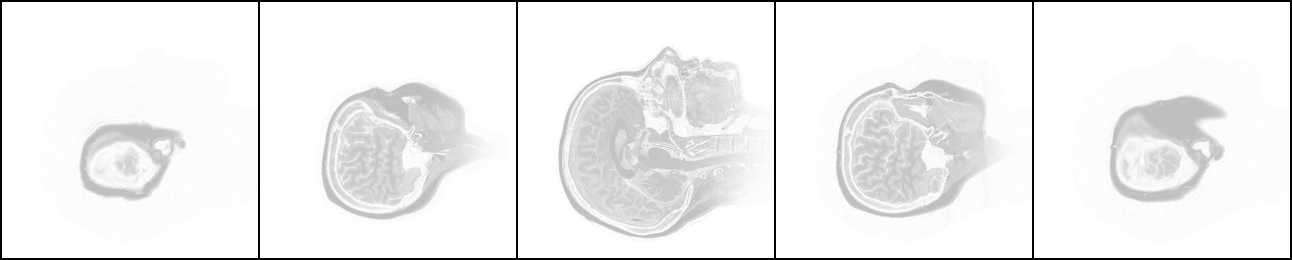

我手头这套头部CT断层扫描片共有109张,是侧卧位的水平断层扫描,从一侧开始至另一侧结束。下图从左至右分别是第11张、第21张、第55张、第89张、第99张。不难看出,中间的一张面积最大,是鼻梁正中的断层图片,鼻尖朝向图片上方,越往两侧的图片,面积越小。